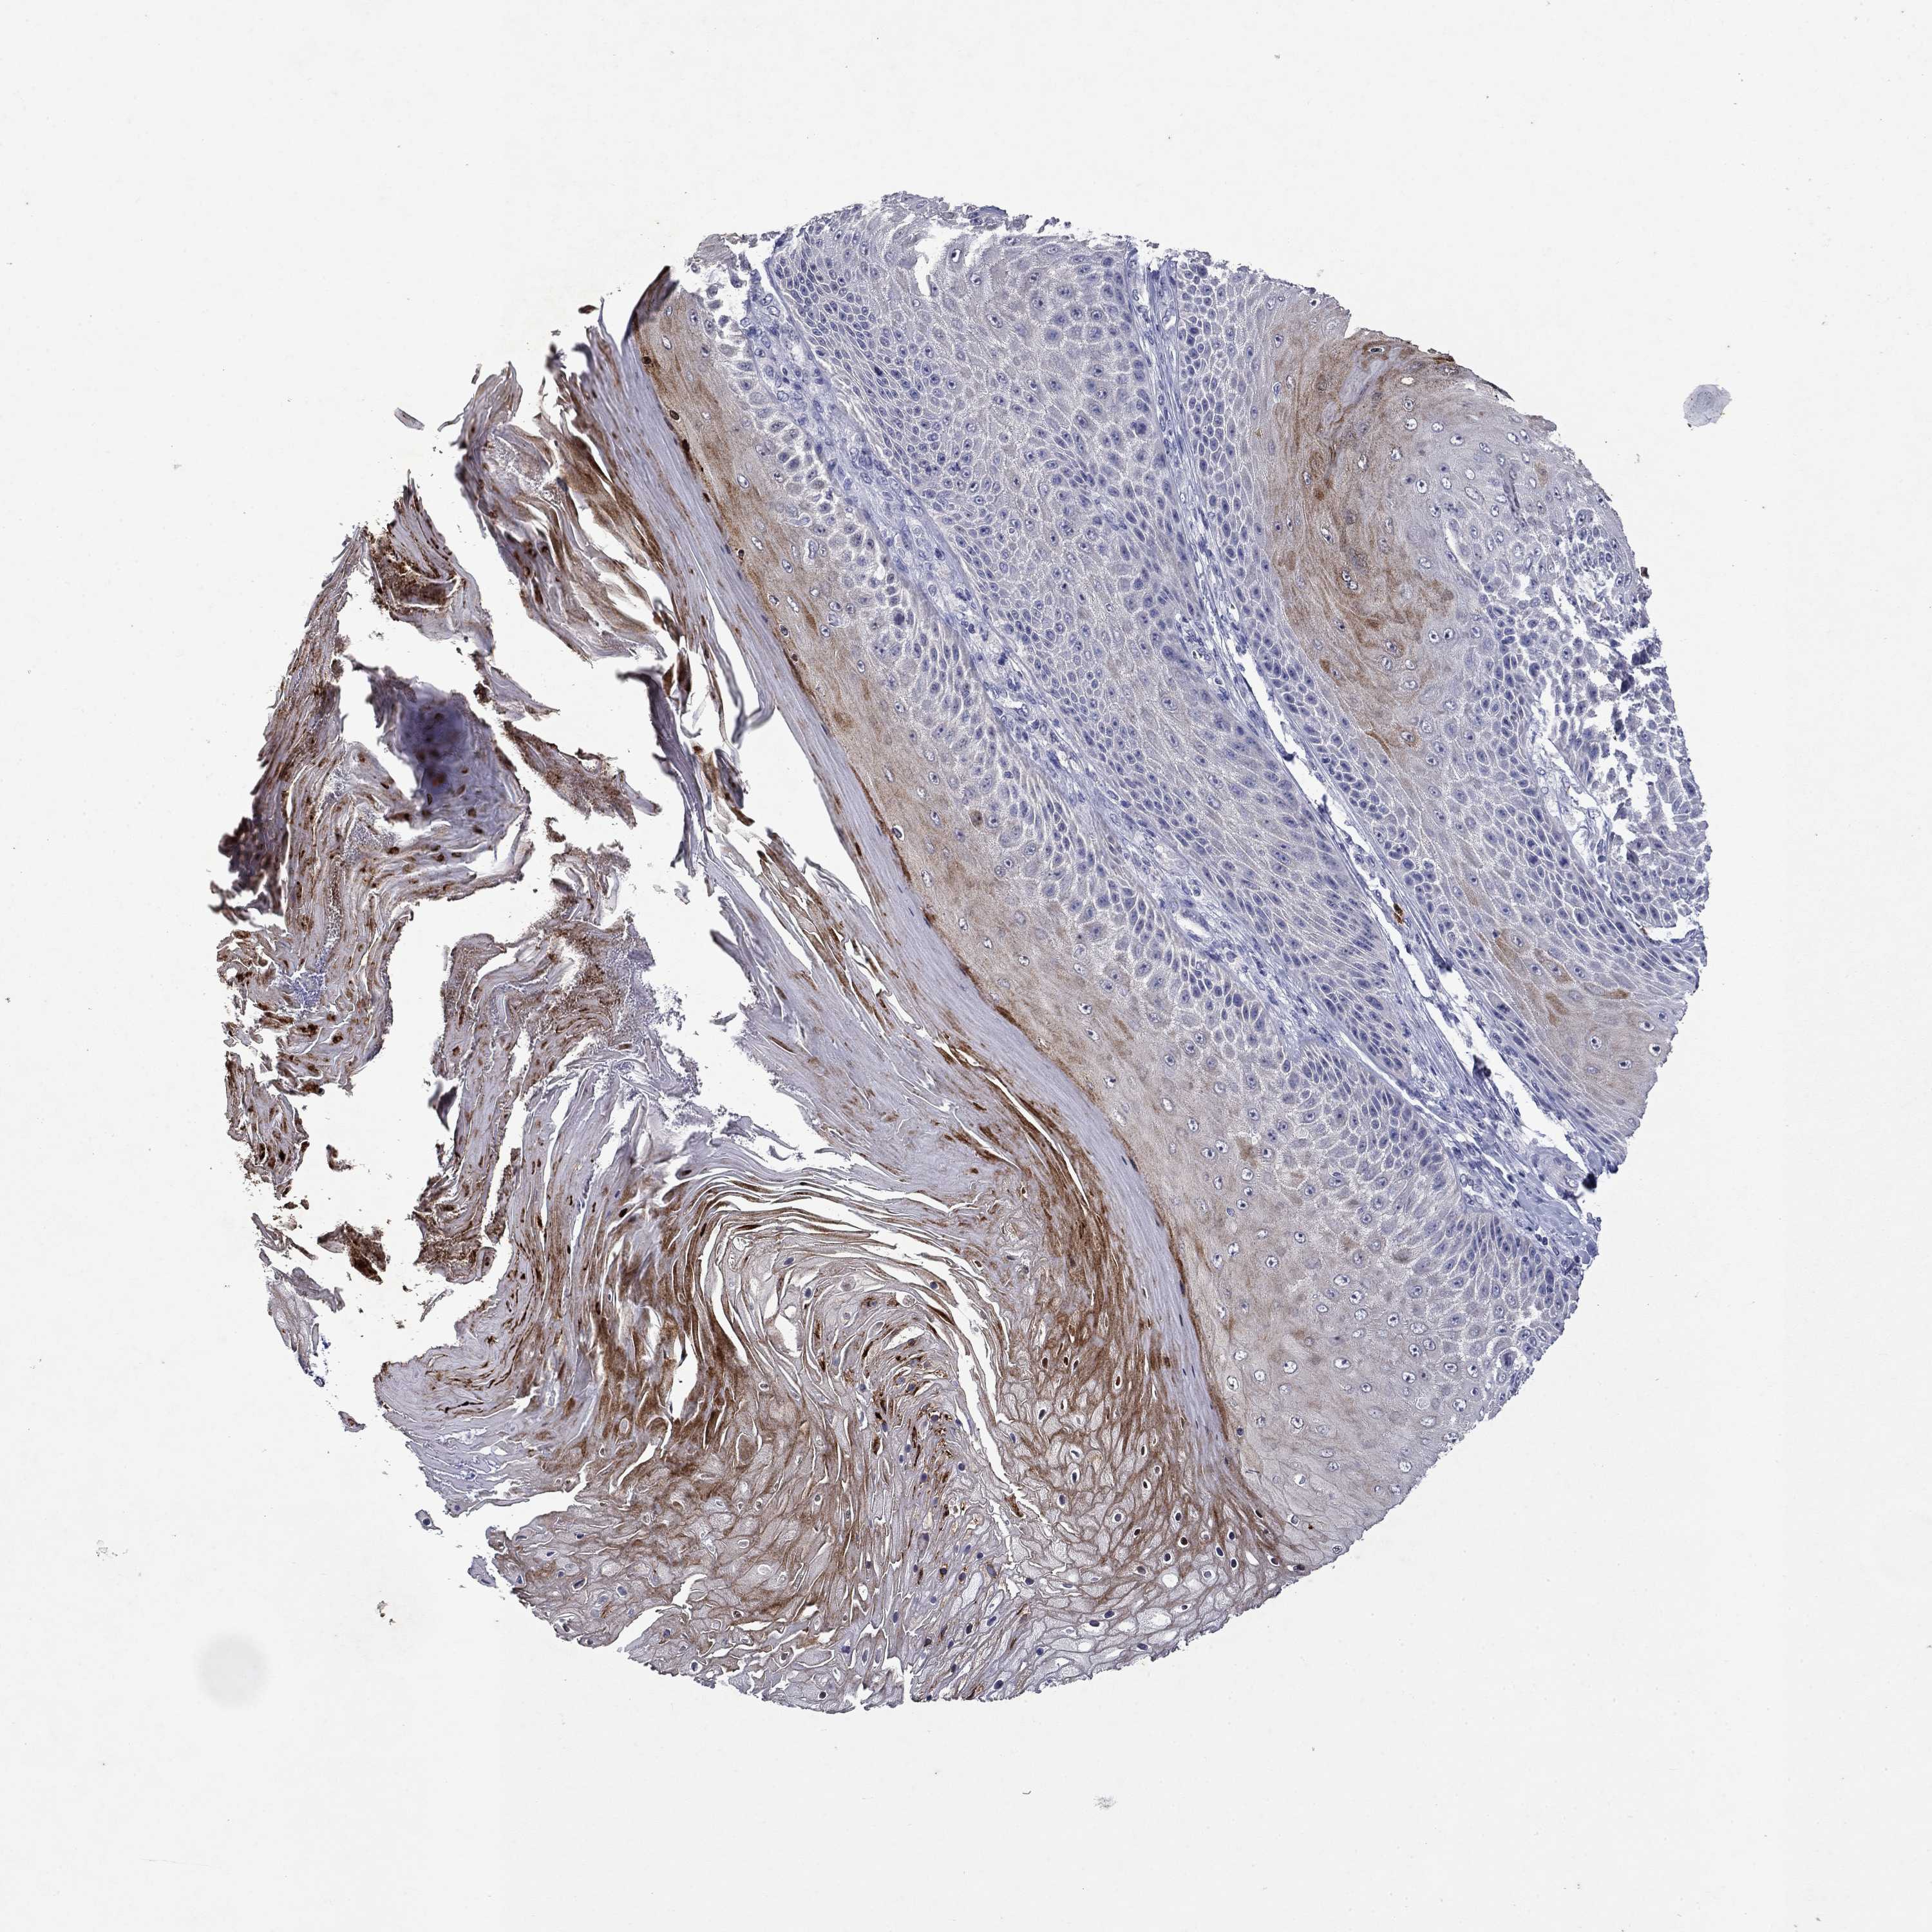

SKIN CANCER - Protein expressioni

A mouse-over function shows sample information and annotation data. Click on an image to view it in a full screen mode. Samples can be filtered based on level of antibody staining by selecting one or several of the following categories: high, medium, low and not detected. The assay and annotation is described here.

Antibody stainingi

Antibody staining in the annotated cell types in the current human tissue is reported as not detected, low, medium, or high, based on conventional immunohistochemistry profiling in selected tissues. This score is based on the combination of the staining intensity and fraction of stained cells.

Each image is clickable and will lead to virtual microscopy that enables deeper exploration of all samples and also displays staining intensity scores, fraction scores and subcellular localization as well as patient and tissue information for each sample.

Squamous cell carcinoma, NOS